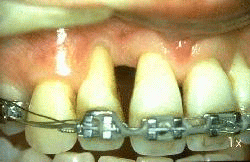

Mujer de 24 años de edad  que ha padecido  periodontitis juvenil desde los 16 años. Las lesiones periodontales se han tratado repetidamente durante los años precedentes y ella ha desarrollado una nueva  patología periodontal en el incisivo lateral derecho superior. Las profundidades de bolsa al sondaje de ese diente es de 4-10 mm  Un colgajo se ha levantado hasta la línea mucogingival y se ha expuesto el hueso maxilar. La pérdida de ligamento periodontal es severa en  mesial y distal  del lateral. En distal se observa un defecto óseo.

Otro colgajo se ha levantado en palatino. Se observa la pérdida del ligamento periodontal en  mesial y distal del lateral. Nótese el defecto óseo en forma de cráter en mesial del lateral.